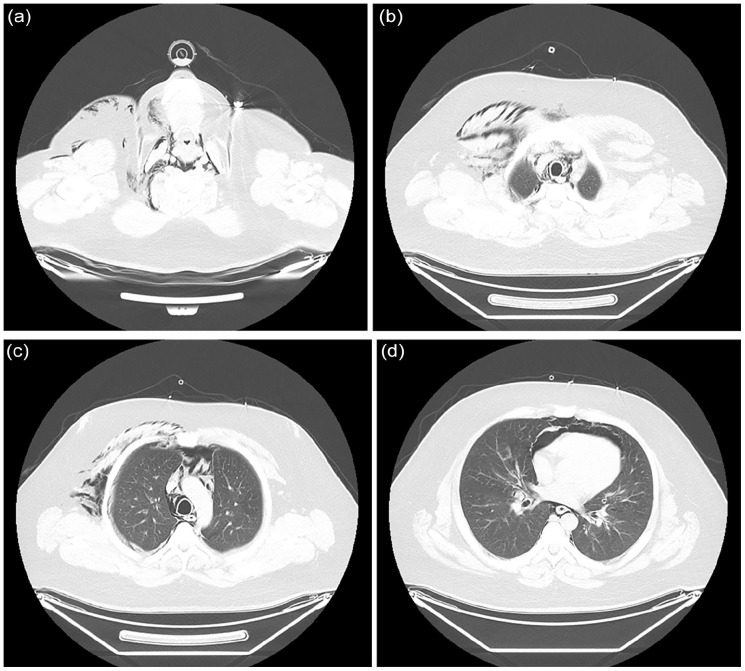

Spontaneous pneumomediastinum (SPM) is a rare, self-limiting condition that can be complicated by pneumothorax, pneumopericardium, and subcutaneous emphysema. This case describes a 25-year-old man with a chronic marijuana use history who developed SPM after a recent respiratory infection. Imaging showed significant pneumomediastinum, pneumopericardium, and small pneumothoraces bilaterally. Despite these findings, he remained stable and was treated conservatively with oxygen supplementation, analgesics, and close monitoring. By day 6, his condition had nearly resolved, and he was safely discharged. This case emphasizes the importance of considering SPM in young patients with acute respiratory distress and reinforces the value of computed tomography scans in promptly diagnosing and managing the condition without invasive interventions.